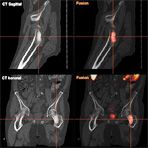

Osteoplastic Metastasis of Prostate Cancer in Choline PET/CT

5. Radionuclides are most appropriate for patients who have several sites of painful osteoblastic metastases (like those that are commonly associated with prostate cancer) that cannot be safely treated with EBRT.